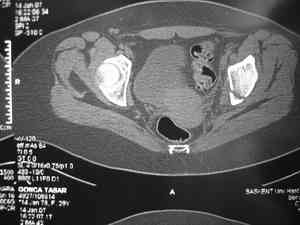

Обследование дополнительными снимками: прямая, инлет и оутлет, а КТ срезы покажет имевшиеся мозольные перемычки и истинное смещение в крестцово подвздошном сочленении.

Дорогой Андрей. Мы имеем дело с комбинированной (ротационно и вертикально) нестабильностью таза со смещением правого гнемипелвиса. При таких переломах, фиксация только переднего полукольца вне зависимости от метода фиксации, как уже было сказано Djoldas Kuldjanov, M.D., не может создать адекватной фиксации. И перелом пластины был вполне ожидаемым после активизации пациента. Смещение сохраняется, и по-видимому не 2 см., а все 4, если не более. Разница всего (+2 см) по конечностям как вы указываете, скорее скомпенсировано позвоночником и протезом. Дополнительные снимки или КТ исследование помогли бы уточнить степень смещения с точностью до мм., выявить перелом поперечного отростка пятого поясничного позвонка, или помимо разрыва правого крестцово-подвздошного сочленения выявить перелом боковой массы крестца справа и т.д. При возможности, конечно, все это желательно сделать. Но мало что изменится с практической точки зрения, т.к. задача - это низведение репозиция и надежная фиксация правого гемипелвиса. Учитывая плачевный опыт стержневого аппарата, давность травмы совершенно очевидно, что поставленная задача достижима при открытой репозиции и одномоментной фиксации переднего полукольца с артродезированием правого крестцово-подвздошного сустава. Операция выполняется в положении больного на здоровом боку или полубоку из расширенного трансоссального подвздошно-пахового доступа с переходом на лонное сочленение доступом по Pfannenstiel. Указанный доступ обеспечивает подход к крестцово-подвздошному сочленению как спереди так и сзади. После артродезирования выполняется синтез лонного сочленения. Клинический пример

Спасибо за клинические примеры и комментарии. Если честно то просто восхищен представлеными R-ммами (классно сделали!!!). По поводу обсуждаемого больного: конечно КТ и дополнительные R-ммы сделаем. Но хочу напомнить, что после травмы прошло более 6 лет, на сегодняшний день клинически еще и R-ки признаки нестабильности эндопротеза( как бедренного компонента так и чашки). Хочется определиться как делать в аппарате или одномоментно открыто. Лично я склоняюсь к аппаратному лечению на первом этапе.